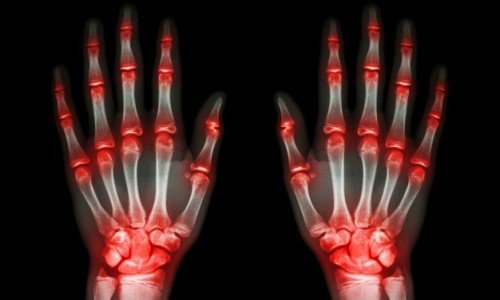

Думата „артрит“ идва от гръцкото „arthro” – „става“ и „it is” – “възпаление“. Днес артритът обединява цяла група болести. Така например остеоартритът възниква след травма на ставата, при възпалителен процес в ставния джоб или при остаряване на организма. Ревматоидният артрит е автоимунно заболяване, при което защитните механизми на тялото не разпознават „своите“ клетки и атакуват собствените си стави. Причината за артрит невинаги може да бъде установена. Така например артритът в юношеска възраст често се нарича идиопатичен, тъй като основната причина за появата му не е ясна. Не е изключено роля да играят вродени и генетични фактори.

Както и да се развие артритът, той носи много неприятности. Постоянна болка, „въртене“ в ставите, ограничаване на тяхната подвижност, деформация – това съвсем не е всичко. При артрит е трудно да се возим в обществения транспорт, не можем да спортуваме или да правим любимите си неща, смяната във времето ни носи безсънни, болезнени нощи. За да преборим симптомите, трябва да използваме лекарства и мазила.